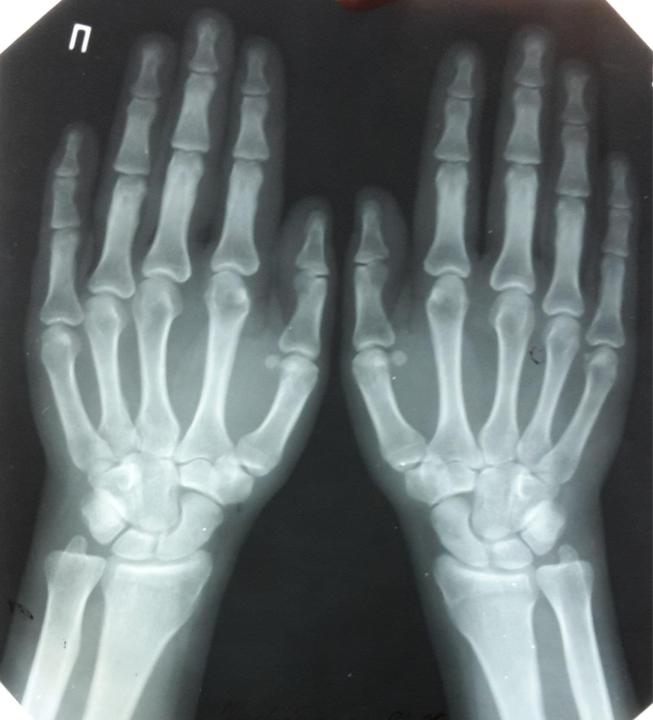

- Симметричное поражение лучезапястных, проксимальных

межфаланговых суставов -

типичное

проявление

ревматоидного артрита.

С помощью рентгеновского метода выявляют такие признаки воспаления, как эпифизарный остеопороз, сужение суставных щелей, костные эрозии, остеолизис, анкилозы. В последние годы широко используют КТ, УЗИ, МРТ.